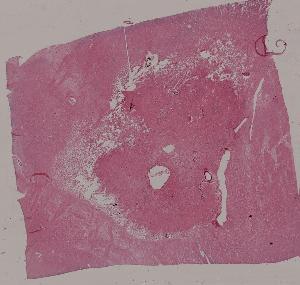

7. Liquefaction necrosis of the brain